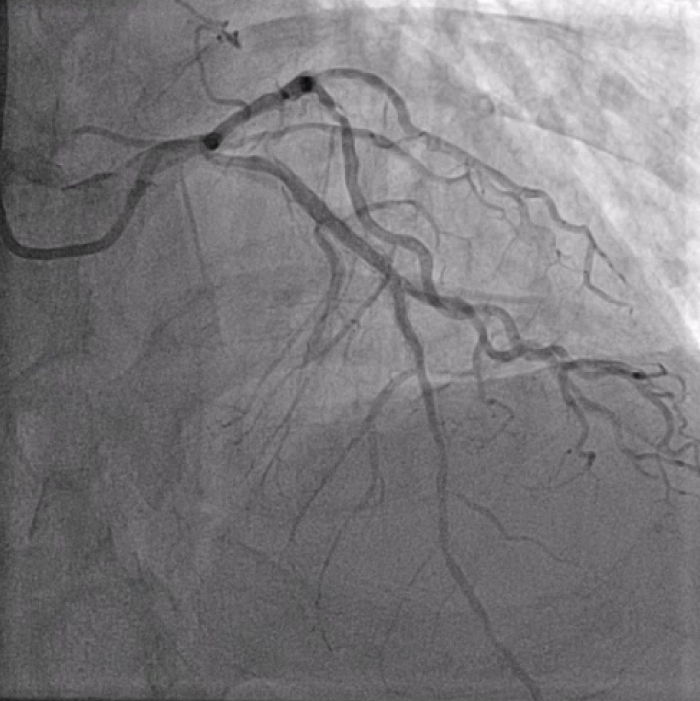

Distal LM intermediate disease, significant proximal LAD ISR, significant mid LCx stenosis. Diffuse high-grade RCA disease (proximal to distal into RPDA). Calcific and angulated proximal RPDA.

In view of severe left ventricular dysfunction, a 40cc IABP was inserted via the right common femoral artery for mechanical circulatory support during PCI. A 6Fr AL1 guide catheter was advanced via the right radial artery to selectively cannulate the right coronary artery (RCA). A Runthrough NS coronary guidewire was advanced into the distal R-PDA. Balloon angioplasty was performed from RPDA back to proximal RCA using a 2.5x15mm Sapphire3 NC balloon to 12atm. A Boston Scientific Opticross HD 60MHz IVUS catheter was advanced into the distal RPDA and intravascular imaging performed. Unfortunately, upon completion of the pullback run, the IVUS catheter could not be withdrawn. The IVUS catheter was stuck on the calcific and angulated segment in the proximal RPDA. Despite use of focused force technique, parallel ballooning, the IVUS catheter could not be withdrawn. During the attempts, the IVUS catheter inadvertently broke, leaving a short segment of the catheter in the RPDA. Check angiography showed no flow impairment. Thus, proximal to mid RCA was stented using a 3.0x38mm DES and a 3.5x48mm DES. Due to long procedural time, decision made to stage further PCI to the next day. The following day, PCI to LAD was performed uneventfully. The RCA was cannulated using a 7Fr AL2 guide catheter via right radial artery. A Sion Blue ES guidewire was advanced into the RPDA. A 6Fr Liquid guide extension catheter was advanced across the stented segments. A 3.2Fr EnSnare used to withdraw IVUS.